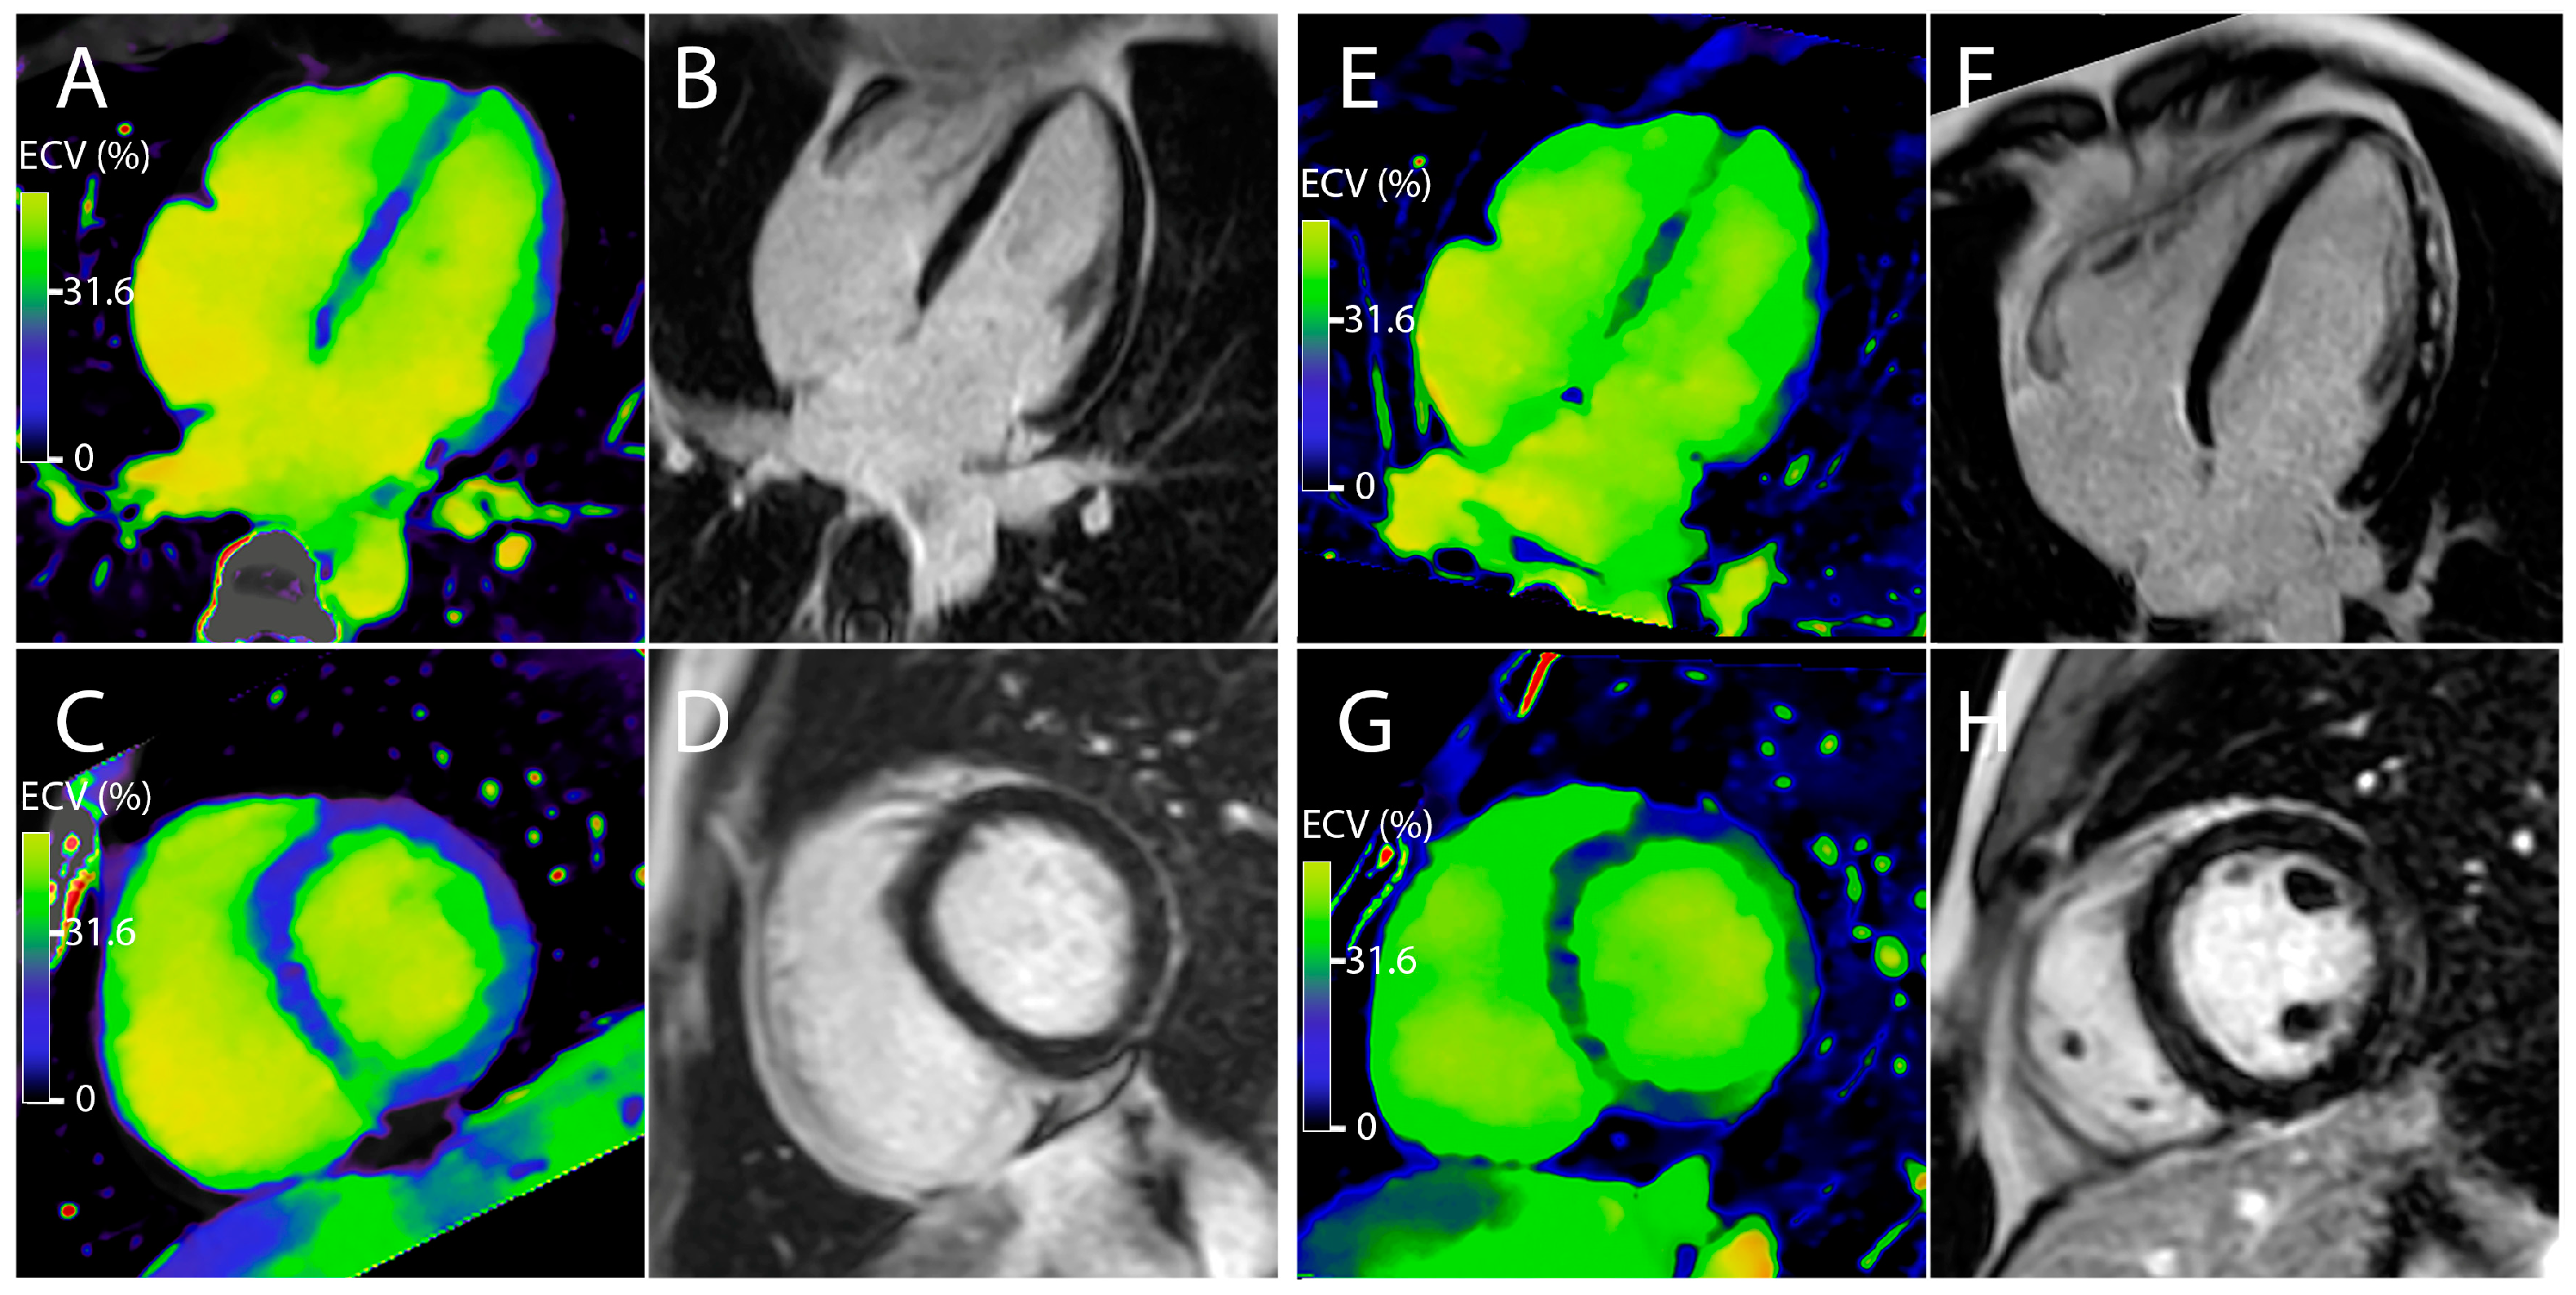

3.2. Measurement of the Myocardial Inflammation

3.3. Correlation between ECV and the Different Parameters